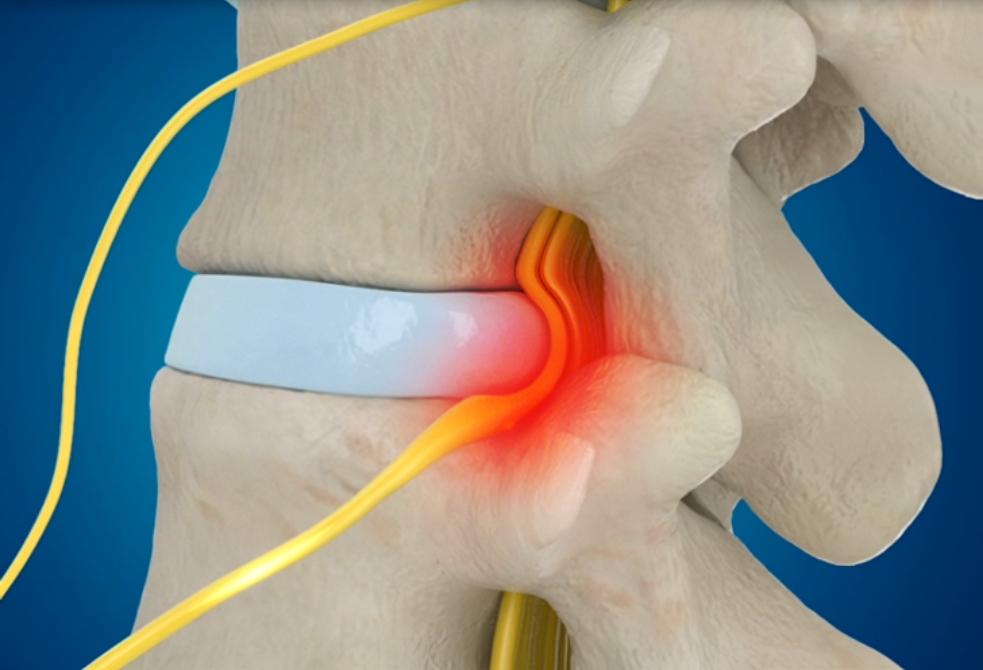

자생 비수술 한방통합치료 후

터진디스크가 흡수된 모습

비수술 치료만으로

터진 디스크 흡수

튀어나온 디스크 대비,

터진 디스크 치료 효과 우수

디스크 흘러내린 정도가

심할수록 흡수 가능성 증가